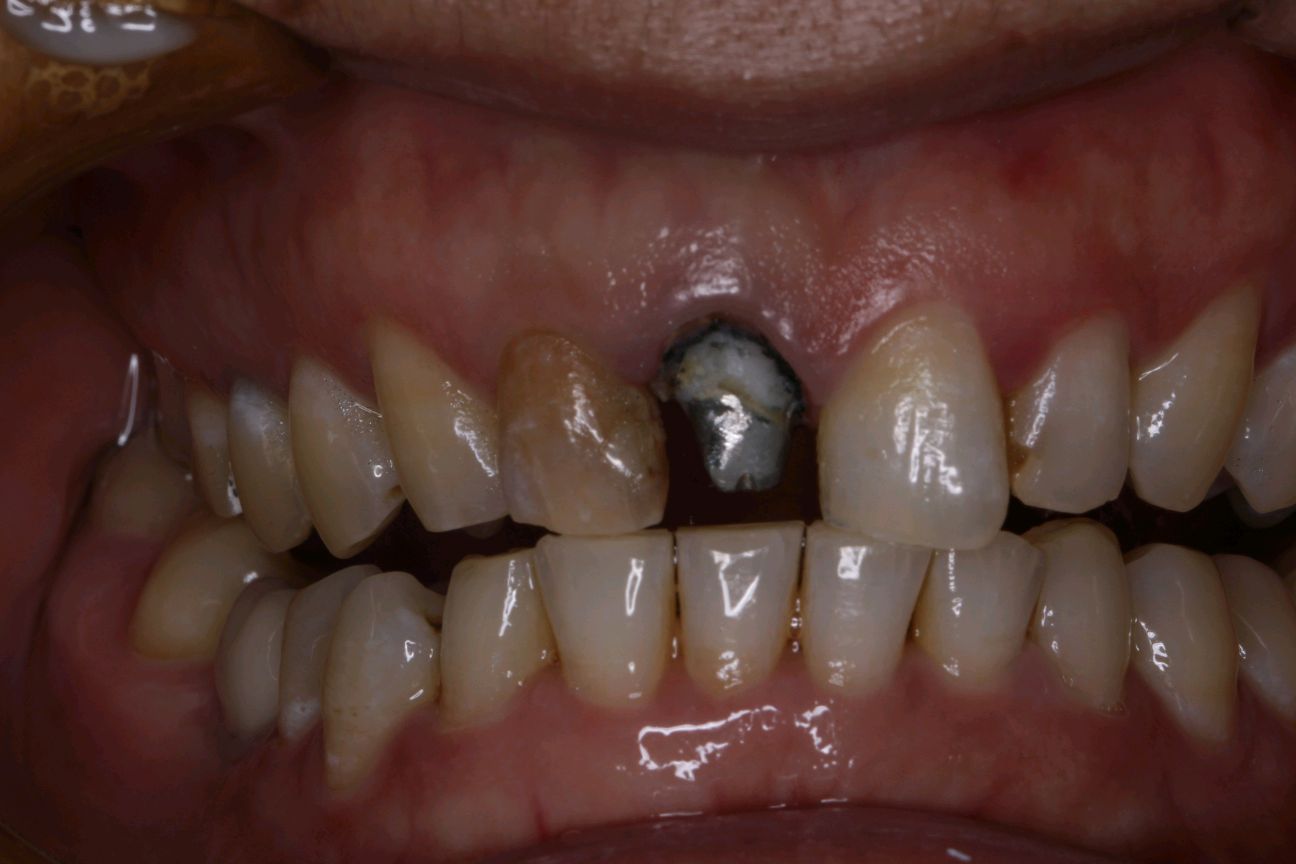

患者女,三十岁,12,11已行根管治疗,未做修复。牙齿发生了变色。其原因是牙齿出现神经炎症或坏死,经过根管治疗后,牙齿会失去来自牙髓的营养供应。这就好比一棵树一旦失去了根系,就会逐渐枯萎一样,慢慢的色泽也会发生变化。死髓的牙齿由于缺乏活力,会逐渐变色,甚至变黑,影响美观。21,23近中龋坏可行全瓷贴面,减少基牙的磨出面积的同时又能更好的恢复牙齿的自然色泽,使牙齿看起来更加健康和美观。

术前